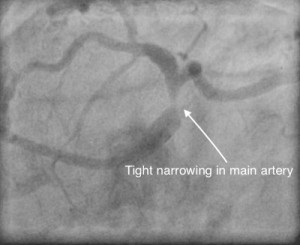

Left main coronary artery is the main artery in the left side that divides into two branches which supplies blood to most part of the heart. There are situations in which this is severely narrowed or blocked and would need attention. Previously, most patients were sent for coronary artery bypass surgery, but with advances in stent technology and the expertise available, angioplasty with stents are more and more performed nowadays to treat this condition. This can also be done, if the patients are considered too high risk for surgery or in emergency situations. Considering this is the largest coronary artery in the heart, it needs special attention and assessment to do the procedure to obtain excellent result.